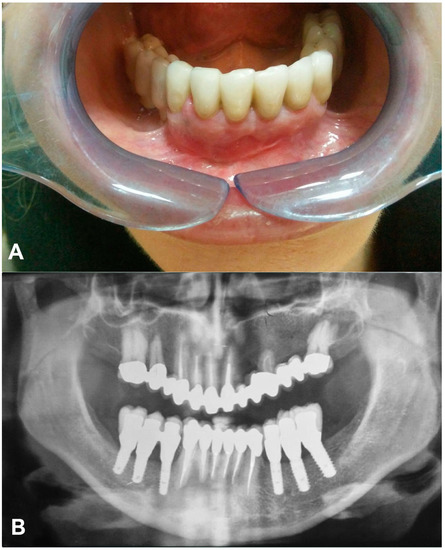

2. Case Report

- Implant-supported prostheses from 3.4 to 3.6 and from 4.4 to 4.6.

- Prosthetic rehabilitation on dental support from 3.3 to 4.3. Metallic endocanalar posts in 3.3, 4.2, and 4.3.

- Endodontic treatment on 3.1, 3.2, 3.3, 4.1, 4.2, and 4.3.